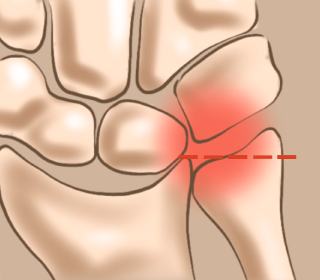

손목관절에는 두 개의 큰 뼈인 요골과 척골이 있는데 손목의 과도한 사용이나 외상, 퇴행성 변화 등으로 요골이 단축되고 척골이 상대적으로 길어져 척골과 수근골이 충돌하면서 통증이 나타나는 질환입니다.